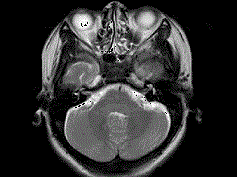

问题 女,41岁,阵发性头痛伴恶心、呕吐20余天.CT影像如图,最可能的诊断为 ( )

选项 A、双侧筛窦息真菌感染 B、双侧筛窦过敏性炎症 C、双侧筛窦炎 D、双侧筛窦未见明显异常 E、双侧筛窦息肉

答案 C